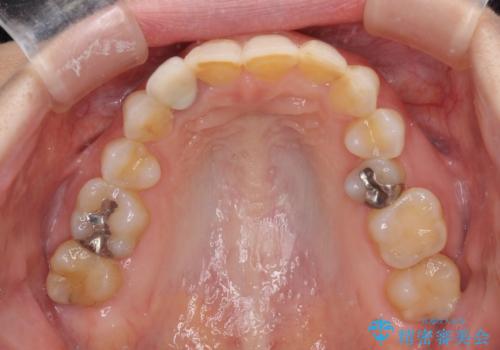

- 前歯のクラウン周りに歯肉が腫れていることを気にして来院された患者様です。

元々磨き残しによる歯肉の腫脹がありましたが、クラウンが歯肉深くに装着されていたため、特に腫脹が目立っていました。

仮歯に置き換えた際に歯周外科処置を行い、歯肉の腫脹が落ち着いたことを確認してオールセラミッククラウンにて補綴することとしました。